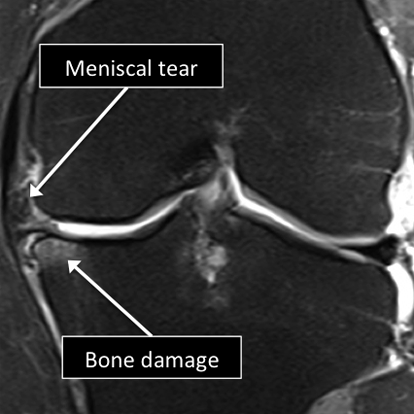

MRI allows us to see many of the different structures in the knee.

Many injuries or diseases affecting those structures can be diagnosed using MRI.

Common things include meniscal tears, ligament tears or degeneration, osteoarthritis, tumors, among many others.

Knee MRI examinations showing normal (top) and abnormal (bottom) meniscus.